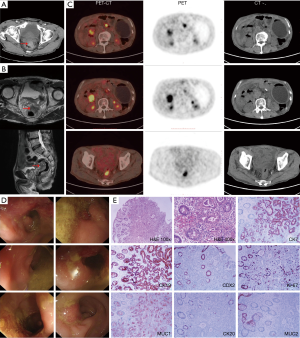

In January 2017, the patient started complaining of bloody stool with increased defecation frequency (3–4 times per day). Chest and abdomen CT on February 17 revealed a high-density shadow in the thickening wall of the cecum (Figure 3A). Magnetic resonance imaging (MRI) of the lower abdomen on February 27 revealed a mass located in the middle and lower section of the rectum, with the peritoneum refolded (Figure 3B). Multiple small lymph nodes around the tumor were noted. A soft-tissue shadow with high metabolic activity in front of the right kidney and multiple enlarged lymph nodes behind the retroperitoneum were observed by positron emission tomography-computed tomography (PET-CT) (Figure 3C). Colonoscopy revealed an irregular mass at about 5–7 cm from the anus in the rectum, occluding 50% of the lumen (Figure 3D). Histological examination (hematoxylin and eosin staining) of biopsy specimens taken from the mass revealed an adenocarcinoma. However, a further increase in serum CA19-9 to 3,426 U/mL prompted us to further explore the possibility of relapse or metastasis of the previous pancreatic adenocarcinoma. Subsequent immunohistological analysis showed the specimens to be positive for cytokeratin 7 (CK7), cytokeratin 19 (CK19), CDX2 protein, Ki-67 protein, mucoprotein 1 (MUC1), and negative for cytokeratin 20 (CK20) and mucoprotein 2 (MUC2) (Figure 3E). These results indicated that the rectum lesion might have originated from the pancreas adenocarcinoma that was previously resected.

From March 9, 2017, palliative radiotherapy (50 Gy/25 fractions) targeting the rectum neoplasm and pelvic lymph drainage was administered; however, in consideration of the patient’s poor physical status, concurrent chemotherapy was not applied. After radiotherapy, the serum CA19-9 level had decreased significantly on April 7 to 1,255 U/mL (Figure 4A). On May 24, the patient received rectal MRI, revealing a slightly shrunken tumor (Figure 4B). On July 7, the patient was admitted to the emergency department for a severely distended abdomen. CT examination revealed an enlarged gastric cavity with retention of contents and an irregular soft tissue shadow in front of the right kidney (Figure 4C). The patient ultimately died on August 28 due to the increased tumor load (Table 1).

A recheck of the previous CT images from November 2017 showed a small, high-density shadow inside the rectal wall (Figure 5A) that was not observed in the images from September 2017 (Figure 5B). Because of the patient’s previous history of rectal polypectomy, the shadow was neglected by both the radiologist and the oncologist.